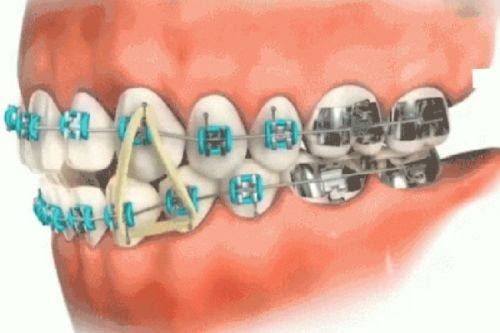

牙齿美容整形多少钱?2026年最新价格揭秘与注意事项! 本文围绕2026年牙齿美容整形价格及注意事项展开。牙齿整形费用参考范围8000 - 30000元,受畸形程度、地区、矫治器材料等因素影响。不同矫治器材料费用有别,国产亲民、进口稍贵、隐形更贵。还介绍了医院医生、治疗方案等影响价格的其他因素。同时给出选择正规机构、与医生沟通等注意事项,助大家选合适方案美牙。 牙齿美白 2026年03月04日 0 点赞 0 评论 7 浏览